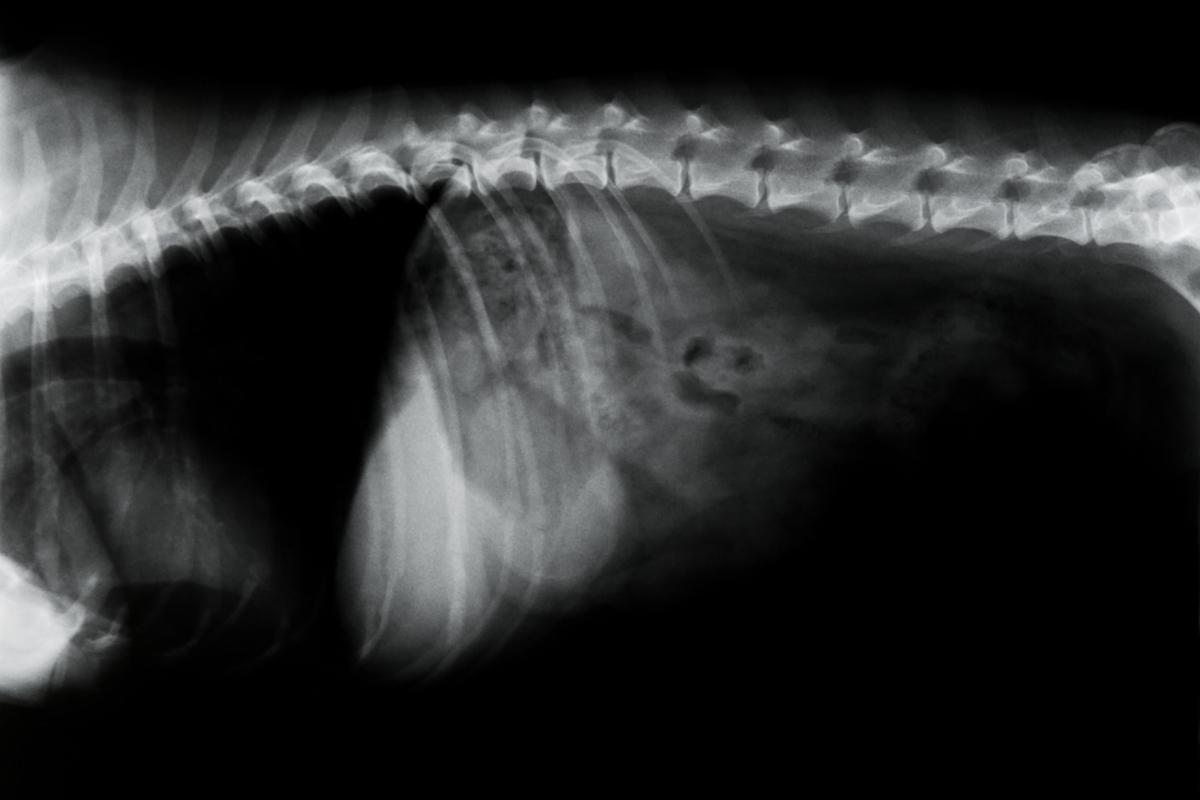

Discopatías

Las principales discopatías o problemas de los discos intervertebrales en los perros son la protrusión o la extrusión del material discal dentro del canal vertebral (hernias discales) o la degeneración de los discos intervertebrales pudiendo causar signos leves incluyendo dolor de columna, paresia y ataxia y graves con la parálisis o la pérdida de la función sensitiva posterior a la lesión.

Los discos intervertebrales se encuentran entre las vértebras, uniéndolas, y rodeados de ligamentos que les dan soporte. Tienen una función de actuar como almohadillas intervertebrales para absorber y amortiguar las fuerzas de choque, permitir los movimientos y unir las vértebras de la columna para formar un conjunto.

Degeneración discal

La degeneración de los discos intervertebrales es más frecuente en las razas que son condrodistróficas como el teckel, el beagle o el pequinés, presentándose con mayor prevalencia entre los 3 y los 6 años de edad. Cuando se produce la degeneración, se pierde elasticidad y pueden calcificarse.

Dependiendo de la localización a lo largo de la columna, la sintomatología variará. Es mucho más frecuente que se produzca en la columna vertebral torácica o lumbar, aunque en el 14-16% de los casos se puede producir en la zona cervical produciendo:

Las degeneraciones torácicas y lumbares constituyen hasta el 86% de los casos y son más frecuentes entre las vértebras torácicas 11 y 12 y la lumbar 1 y 2, cursando con síntomas como dolor del lomo, incoordinación de movimientos y paresias de los miembros pelvianos o posteriores.

Hernia discal

Las hernias discales consisten en una compresión de la médula espinal debido a salidas del disco (extrusión discal en perros) o a abultamientos del mismo (protusión discal en perros).

El tratamiento suele ser quirúrgico además de conservador para descomprimir la médula afectada. Las hernias discales en perros siguen la clasificación de Hansen y las podemos dividir en tres tipos:

- Hernia de Hansen tipo I: aparecen en las pequeñas razas condrodistróficas de columna larga y cortas piernas, como el teckel, el cocker, el pequinés o el caniche toy y se produce una degeneración condroide del núcleo pulposo con posible calcificación del mismo, provocando una extrusión o salida del disco hacia el canal medular, comprimiéndola de forma focal y aguda. Estas hernias suelen ser secundarias a traumatismos como caídas, saltos o golpes bruscos.

- Hernia de Hansen tipo II: se producen en las razas grandes no condrodistróficas como el labrador, el pastor alemán, el bóxer o el rottweiler a edades de 5 a 12 años y desarrollándose una protrusión de forma gradual del anillo fibroso del disco por degeneración crónica (metaplasia fibrosa). Esta compresión de la médula es focal, pero lenta y progresiva.

- Hernia de Hansen tipo III: son las hernias más graves en las que se produce una rápida mielomalacia progresiva por extrusión severa y aguda no compresiva en la que el material sale del anillo fibroso hacia el canal medular de forma brusca y generando inflamación que en muchos casos pueden derivar en una muerte del perro afectado. Suele aparecer tras traumatismos graves como atropellos, golpes o caídas fuertes de gran altura.